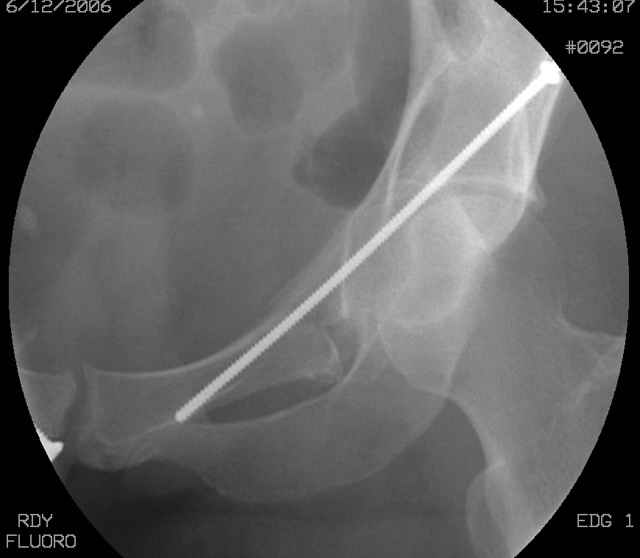

Here's a pic from the foot of the bed and you can see the clamp in the wound and the knee is extended so he must've had a tight rectus. The C-arm is rolled back to an obturator oblique image to reveal the anterior column...we put a slight outlet tilt to combine the images and give a better view of the anterior column...we can see the posterior column limb reduction in the wound, we can palpate the quadrilateral surface limb, and the image demonstrates the anterior column portion...you can adjust the tilt and rotation to image tangentially to the fracture plane if you'd like. We've inserted a 2mm K wire to site the starting point and aim/orientation for the drill and screw

Prone Imaging

same image, just another look.